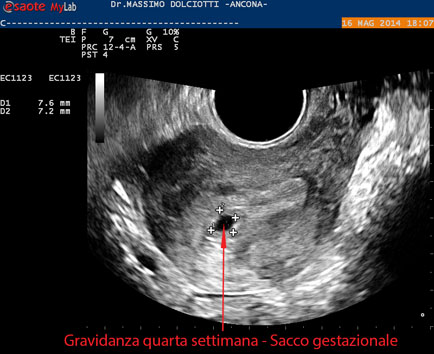

Data inserimento: 19 /05/2014Ecografia del: 16/05/2014 Strumento: Esaote MyLab 50 Gold - Responsabile Linea Cardio Esaote Regione Marche Dr. Franco Fabi Sonda: Endocavitaria Multifrequenza 4-8 MHz Età Paziente: F 27 anni Motivazione dell'esame: amenorrea. Beta HCG = 1.459 mUI/ml. Commento all'esame: le immagini ed il video documentano utero retroverso, con endometrio ispessito e presenza del sacco gestazionale delle dimensioni di 7,6 x 7,2 mm. All'ovaio destro presenza di corpo luteo gravidico con vascolarizzazione aumentata. Conclusioni: gravidanza alla quarta settimana di gestazione (Pregnancy at the fourth week of gestation). Potete esprimere le vostre osservazioni e commenti sul BLOG. Presentazione: Dr. Massimo Dolciotti - Ancona Elaborazione digitale: Andrea Dini - Ancona